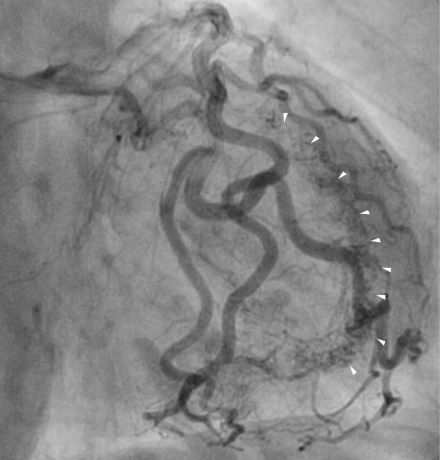

An 85-year-old woman with CCS had angina progression, reaching functional class 3 and frequent need of nitrate use, despite the use of three antianginal drugs. Stress myocardial perfusion scintigraphy showed reversible hypoperfusion in the lateral, inferolateral and inferior LV walls. A coronary angiogram was performed, revealing the absence of obstructions. However, CAF for the LV was identified around the ischemic territory. It was decided to start our Alopurinol protocol for RA. A treadmill test was done before and after the treatment to assess time to angina occurrence and ST segment change. After 3 months, there were an improvement in the threshold and intensity of angina (class 2) and reduction in nitrate need. In a new scintigraphy, normalization of perfusion was observed, and a new treadmill test showed reduction of 4.1 minutes for angina occurrence with an increase of 1.7 mets and no difference in ST change.